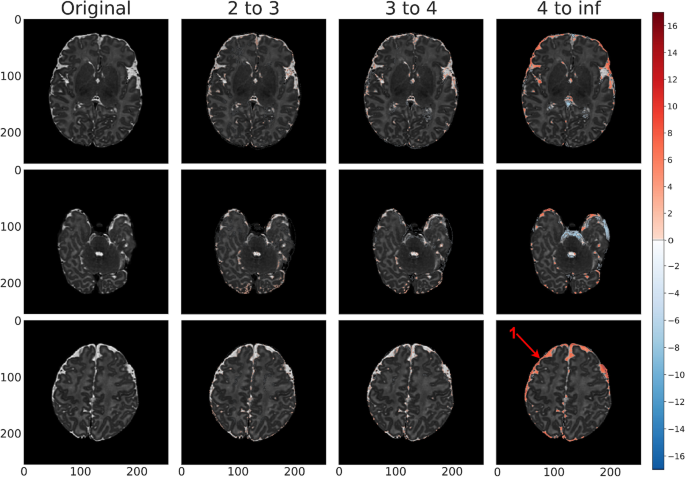

Test (labeled abnormal, gestational birth age of 37 weeks) anomaly detection map for vae_8x8_512 across each standard deviation range. Positive standard deviations of the reconstruction error map are indicated in shades of red and negative standard deviations are indicated in shades of blue. In this example, the peripheral and deep white space as well as asymmetric fluid space (\(3^{+}\) standard deviations, arrow 1) is indicative of volume loss in the left hemisphere. We also see hemorrhage along the tentorium and occipital region (2–4 standard deviations, arrow 2).

This specific anomalous region was identified by our radiologist in an MRI scan of a term birth (39 weeks) subject that was labeled as normal by dHCP. Our model identified an anomaly in the right occipital lobe, which was confirmed by our radiologist. Here we isolate the region across each of our model architectures for the same standard deviation ranges used in Figs. 5, 6 and 7 to determine which approach was most resilient to an anomaly in what was otherwise considered a normal brain.

Figure 7 showed the anomaly detection maps generated by our proposed framework on an abnormal brain. Compared with seemingly normal T2 scans as shown in Figs. 5 and 6, the abnormal scan had higher positive and negative errors (i.e. proposed anomalies) in ventricles and white/gray matter regions, indicating biophysical deviation from a normal signature. This particular scan consists of significant cortical asymmetry along with excessive fluid space. The proposed framework was able to detect the anomalous temporal occipital white matter area in consecutive slices at standard deviation levels 2–3 and 3–4. The highlighted region within the frontal lobe at standard deviation levels 2–3 is consistent with sub-cortical lamination. In addition, the excessive fluid and asymmetry within the Sylvian fissure area was identified at standard deviation level \(4^{+}\). The proposed framework was further able to identify the hemorrhage along the tentorium and occipital lobe parenchyma which was mostly visible in standard deviation levels 3–4 and \(4^{+}\). The proposed framework also identified anomalies in the fluid space surrounding the brain - the fluid assymetry indicates parenchymal volume loss. As a result, this scan can be classified as a class 1B injury (i.e. more extensive cerebral lesions with no involvement of basal ganglia or thalamus, anterior limb of the internal capsule, posterior limb of the internal capsule, or watershed infarction).

The same region of a subject is highlighted across all modeling architectures in Fig. 8. Based on dHCP’s radiologist score, this brain was identified as normal, and as such, was used in the training process. Despite the dHCP label, our proposed framework flagged this specific region as abnormal, mostly visible at standard deviation levels 2–3 on several different model architectures. The same highlighted region could also been seen in the peripheral white matter area at the same standard deviation levels, and appears asymmetrically brighter in consecutive scans.

While the aforementioned metrics confirmed the relatively strong performance of 8x8 VAE architectures, the metrics alone were not sufficient to pick an optimal model. In the clinical interpretation of our results, we found that vae_8x8_512 is able to most effectively identify anomalous regions within the brain, and so we choose this architecture as the best of the ones assessed. This conclusion is best conveyed by Fig. 8. Based on dHCP’s radiologist score, this brain was labeled as normal and was used in the training process. Despite the dHCP label, our VAE models flagged the isolated region as anomalous, particularly in the 2–3 standard deviation range. The same highlighted region can also been seen in the peripheral white matter area and appears asymmetrically brighter in consecutive scans. The highlighted region was smaller in the 3 to 4 standard deviation range but vae_8x8_512 maintained a strong signal in this range, supporting our conclusion that this is the best of our assessed models. These findings show promise in our approach and suggest that (1) our framework had the ability to aid radiologists for more accurate diagnosis, and (2) our modeling approach provides the ability to generalize normal structures within the brain despite the presence of abnormalities in the training dataset.